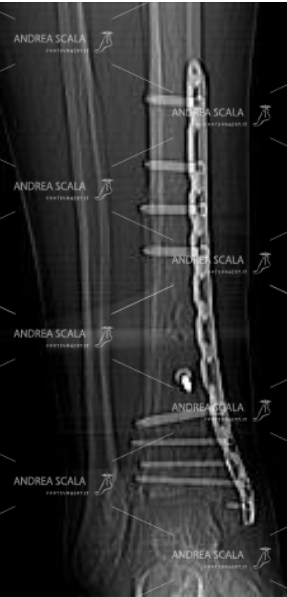

I risultati clinici a distanza non sono omogenei e risultano molto variabili anche in centri traumatologici di grande esperienza. Molto spesso si osservano interventi molto ben eseguiti in cui la frattura risulta ricomposta molto bene con placche e viti disposte in modo adeguato, in cui la mobilità articolare il risultato funzionale risultano molto deludenti sia per il paziente che per il chirurgo.

La frattura risulta ricomposta molto bene con placche e viti disposte in modo adeguato, in cui la mobilità articolare il risultato funzionale risultano molto deludenti sia per il paziente che per il chirurgo.

1) L’INSTABILITA’ ( che caratterizza le fratture del pilone tibiale) comporta scomposizioni secondarie. Questo si osserva nei casi trattati in maniera conservativa oppure con il fissatore esterno, ove è molto difficile mantenere la riduzione una volta ottenuta. Anche alcuni casi trattati chirurgicamente non sono esenti da scomposizioni secondarie che vanificano il lavoro chirurgico.

2) La PRECARIETA’ DELLA VASCOLARIZZAZIONE locale è una delle cause maggiori di mancato consolidamento delle fratture del pilone tibiale. La vascolarizzazione di questo distretto è molto precaria, e una volta interrotta è difficile che possa essere ripristinata.

3) La PSEUDOARTROSI ha sede nello spazio che si viene a creare tra i frammenti ossei della frattura. In alcuni casi è difficile che lo spazio venga colmato dal callo osseo, giacché la vascolarizzazione è stata compromessa al momento del trauma ed i frammenti ossei risultano de-vascolarizzati.